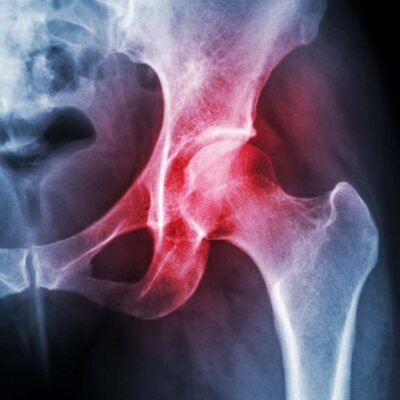

[ad_1] Osteoarthritis affects 530 million people worldwide Puwadol Jaturawutthichai/Shutterstock Drug-delivering nanoparticles might help treat osteoarthritis. In mice with signs of the condition, a single injection